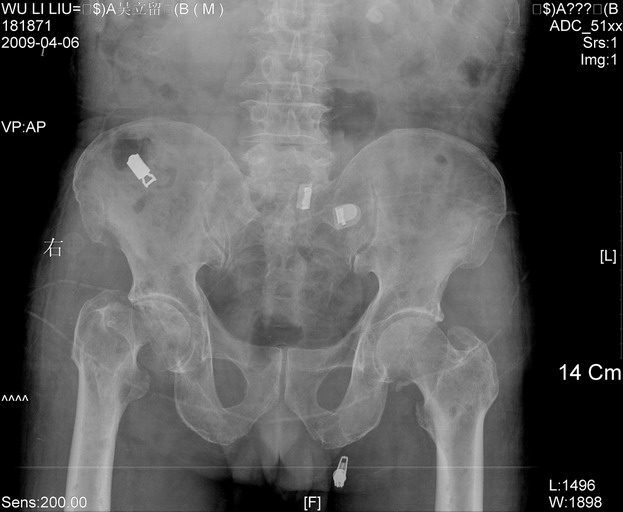

以下是引用zjzjr在2009-4-7 12:13:00的发言:[br]支持多发性转移瘤,右股骨颈骨折,腰椎亦有压缩性骨折.肝内胆管结石伴胆内外胆管扩张,左肾结石.

以下是引用liaoqiang在2009-4-7 8:44:00的发言:[br]考虑多发性骨髓瘤伴肝肺转移、肝内胆管结石、左肾结石、右股骨颈骨折。

以下是引用余辉在2009-4-7 8:52:00的发言:[br]椎骨及骨盆骨质疏松,骨破坏主要累及椎体,各骨破坏较广泛,各病灶边缘均较清晰锐利,血沉增快,白细胞增高.支持考虑多发骨髓瘤,建议查本尿周氏蛋白.[br]胆内胆管及左肾结石[br]右股骨颈骨折,考虑病理性